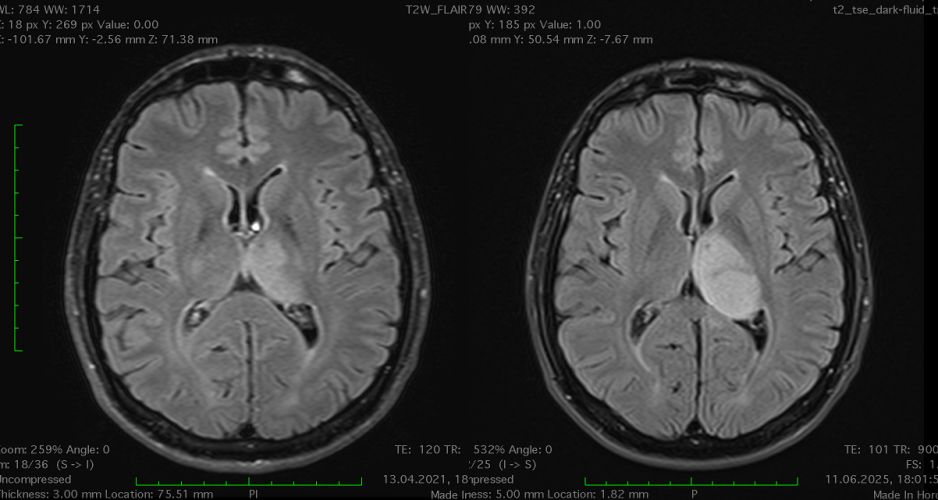

RMN cerebral cu contrast – metoda standard pentru caracterizarea glioamelor. Glioamele de grad mic apar ca leziuni hipointense pe T1, hiperintense pe T2, fără captare de contrast. În mod uzual se consideră că dacă un gliom de grad mic are o zonă cu priză de contrast pe RMN el este de grad III – anaplazic (grad înalt).

Gliom de grad mic talamic stâng progresie în 4 ani